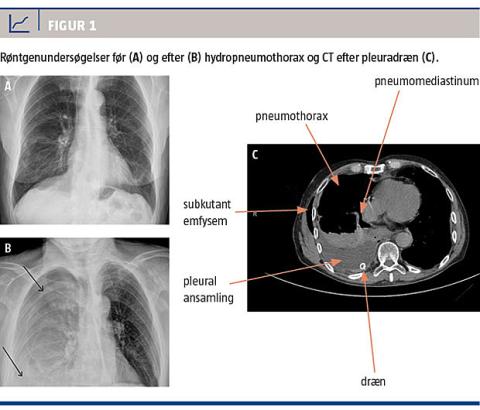

En 78-årig mand med Barretts øsofagus, som er en tilstand, hvor metaplastisk cylinderepitel disponerer til udvikling af cancer i øsofagus, hvilket er en yderst sjælden årsag til spontan øsofagusruptur [2], blev indlagt i mave-tarm-kirurgisk regi på grund af pludseligt opståede tiltagende kaffegrumslignende opkastninger. Ved indlæggelsen var han ikke akut påvirket. Ved lungestetoskopi og røntgenfotografering af thorax (Figur 1A) fandt man normale forhold.

Efter halvandet døgns indlæggelse blev patienten pludselig respiratorisk dårlig med faldende saturation, stigende puls, høj respirationsfrekvens og brystsmerter. En røntgenoptagelse af thorax viste en hydropneumothorax i højre halvdel af thorax (Figur 1B). Den vagthavende ortopædkirurg anlagde et pleuradræn, hvorigennem der blev udtømt 1,3 l brunligt, syrligt lugtende ventrikelindhold. Det udtømte materiale blev sendt til mikroskopi og resistensbestemmelse, hvor man fandt abdominalindhold med en blandingsflora af bakterier.

Ved en CT med kontrast af thorax og abdomen dokumenterede man ruptur i den midterste del af øsofagus og luft i mediastinum og hydropneumothorax i højre halvdel af thorax (Figur 1C).